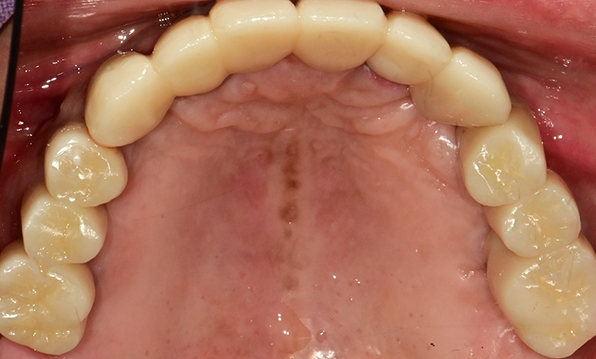

정확성 높은 식립의 노하우

3D 디지털 진단을 통한 체계적인 계획

전체 임플란트는 위턱과 아래턱의 교합, 잇몸뼈의 상태 및

얼굴 변화 등 모든 것을 고려해 식립해야 합니다.

서울더자연치과는 3D 디지털 기술의 정밀 진단을 바탕으로

수술 계획을 세워 수술을 집도합니다.

잇몸뼈 충분히 이식 후 임플란트 식립

성공을 위한 노하우, 잇몸뼈 재건 기술

이 때, 치조골 이식을 병행하여 잇몸뼈 재건 후 안정적인 임플란트 식립을 하고 있습니다.

치료기간 : 2021.04.12~2021.09.15